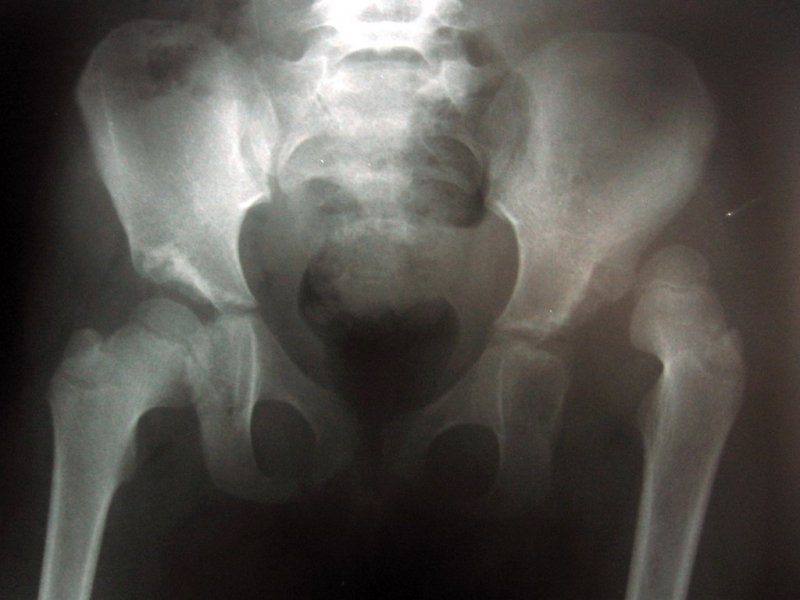

Помимо анализа медицинских историй и визуального осмотра, применяются диагностические методы: рентгенография тазобедренного сустава, ультразвуковое исследование и магнитно-резонансная томография. Эти методы используются для диагностики патологии у детей старше трех месяцев.

Диагностика патологии

Для выявления врожденного вывиха у младенцев специалисты проводят комплекс исследований. Поскольку это заболевание может передаваться по наследству, врач внимательно анализирует медицинские истории родителей. Важным этапом диагностики является изучение информации о течении беременности и процессе родов. Затем осуществляется тщательный осмотр малыша. Для определения степени тяжести недуга проводится детальный опрос родителей, что позволяет установить точное время появления первых признаков.